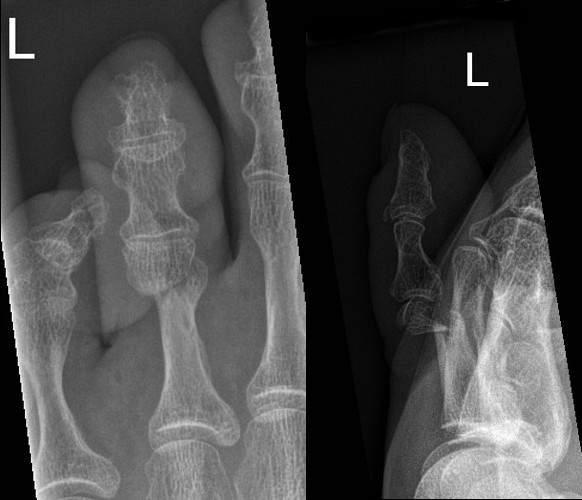

Other phalangeal fractures (including distal phalangeal fractures of the big / 1st toe)

Angulated Salter-Harris II fracture of 5th proximal phalanx

Dorsally displaced transverse fracture of neck of 3rd proximal phalanx

- Consider reduction if significantly angulated.

- Buddy strap and Darco walking shoe or sturdy shoes with no specific follow up.